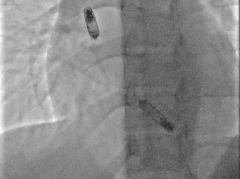

最终植入影像:

RAO30

LAO30